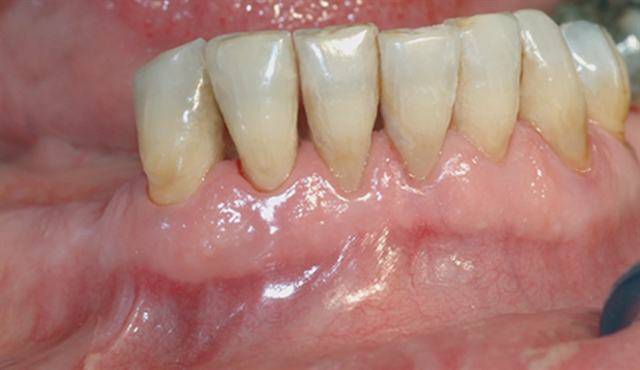

Bentapet bekreftes av et røntgenbilde – skaden er her så stor at tannen må tas bort.